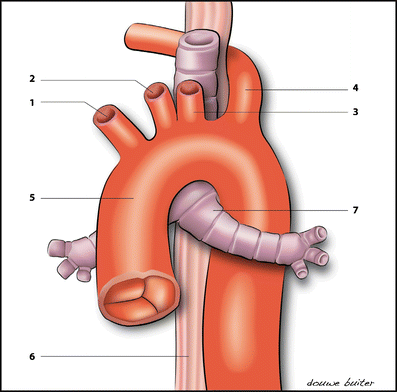

Động mạch dưới đòn phải lạc chỗ là gì?

Đây là một biến thể giải phẫu của quai động mạch chủ.

Bình thường, động mạch dưới đòn phải xuất phát từ thân cánh tay đầu. Trong trường hợp lạc chỗ, mạch máu này xuất phát trực tiếp từ quai động mạch chủ và đi phía sau khí quản trước khi tới tay phải.

Đây là thay đổi về vị trí xuất phát, không phải dị tật tim cấu trúc nặng.